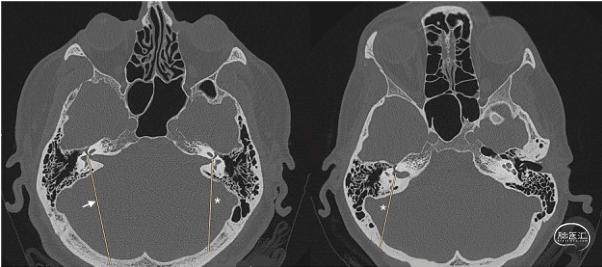

该研究回顾性分析33例取“公园躺椅体位”行乙状窦后开颅切除听神经瘤的患者临床资料。依据患者术前术后的CT,以起始于内听道底、走行于迷路的后方到达枕骨鳞部的内听道底—迷路线(FLL),作为确定开颅骨窗后缘的位置(图1、2、3、4);并用logistic回归模型评估开颅骨窗的位置与内听道底暴露概率的相关性。

图2. 迷路和内听道的空间关系。